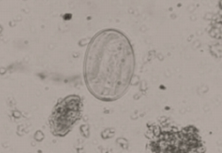

虫卵は無色で卵殻が薄く、4~16個の細胞を含み、おおきさは73~89 x 34~45㎛です。